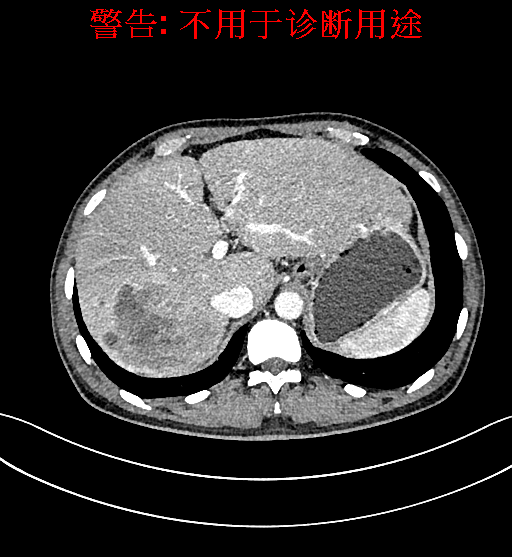

上腹部增强CT示肝右叶多发低密度结节、片团影伴肝门区、肝胃间隙多发肿大淋巴结,原发性肝Ca可能性大,请结合临床肝硬化肝脏小囊肿。

术前CT检查:

平衡期